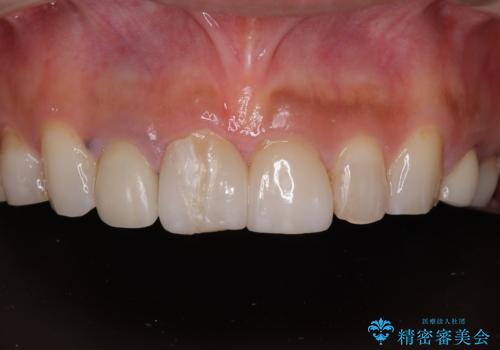

- 「前歯をきれいにやり替えたい」とご相談いただいた40代女性の症例をご紹介します。

患者様は過去に装着されたラミネートベニアが割れてしまったことに加え、土台との間に隙間が生じており、適合が不良な状態でした。

このままでは見た目だけでなく、むし歯や歯周病のリスクが高まってしまいます。

そのため当院では、上顎左右中切歯を適合精度の高いオールセラミッククラウンにて再補綴する治療をご提案し、実施いたしました。